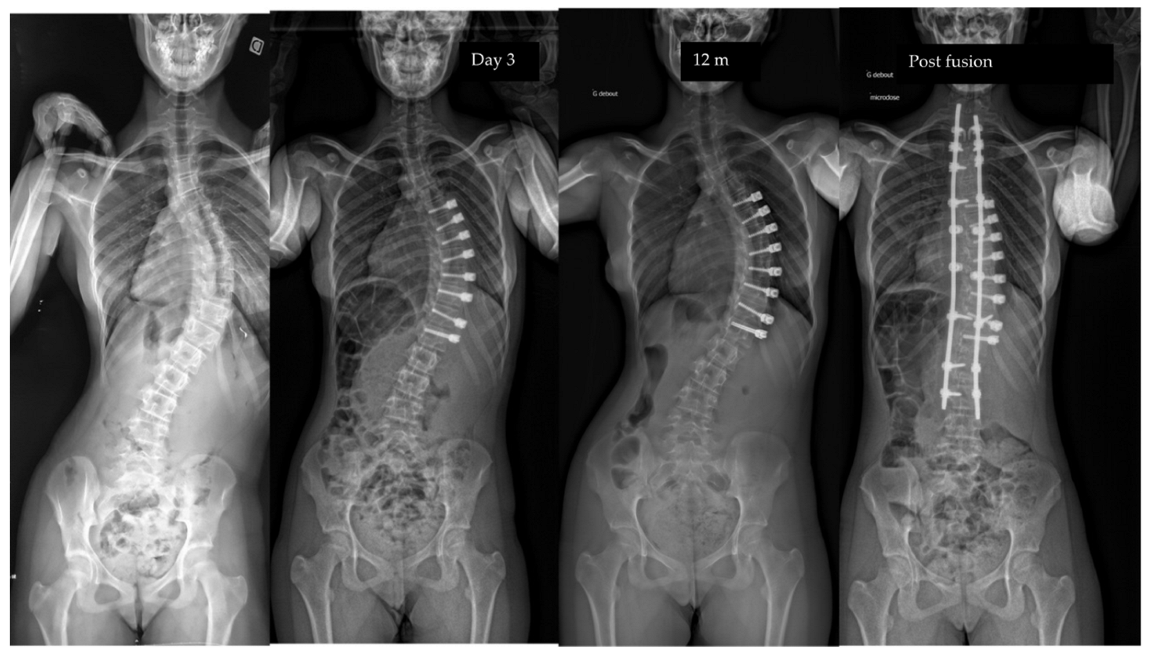

| Major curve | 49°(8,9°) | 27°(12°) | 22°(12°) | 19°(14°) | <0.01 |

| Curve progression | 5 (2 adding-on) (5%) | Thor. | Fusion | 1 y po |